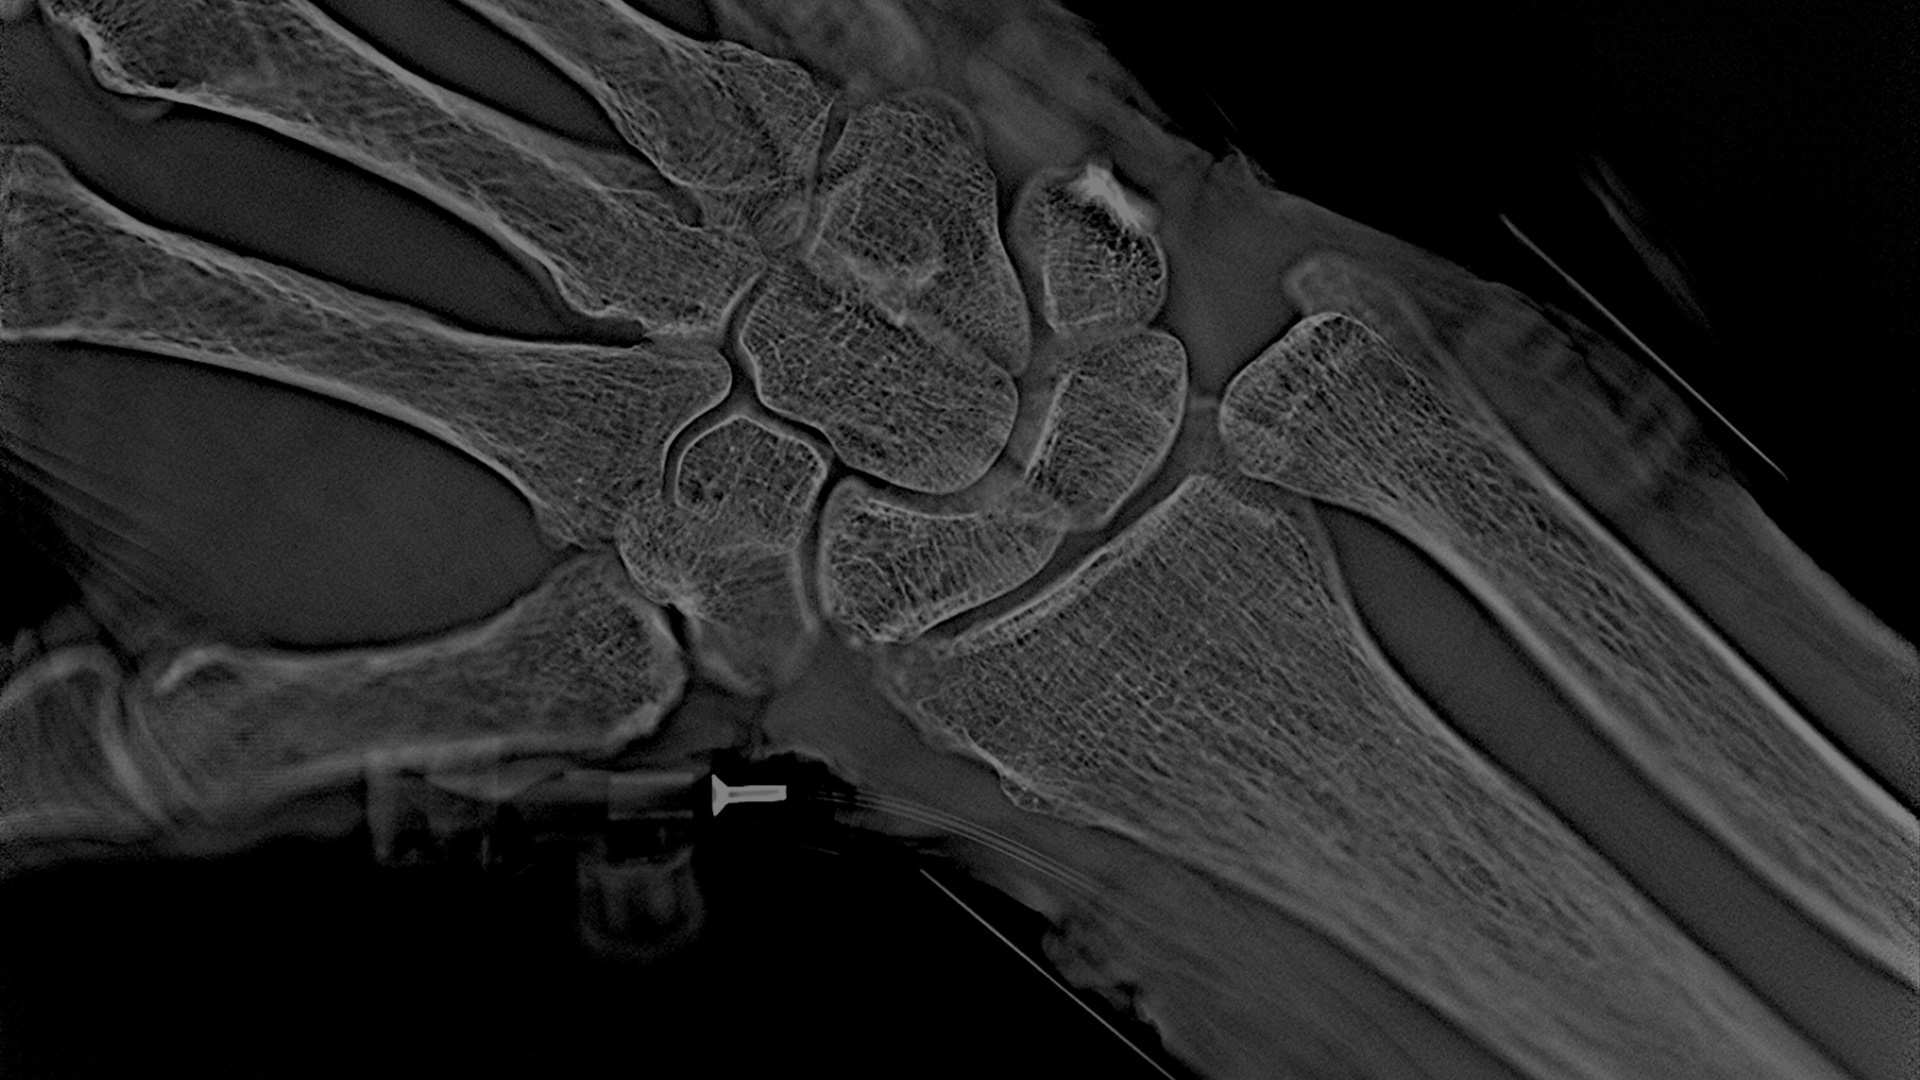

The first Adaptix medical product is a Digital Tomosynthesis Orthopedic imaging system. It is a portable, low-dose imaging system capable of delivering fast, lower-cost, X-ray imaging at the point of patient care. Developed specifically to offer 3D X-ray imaging of hands, elbows and feet at a fraction of the radiation dose and per-study price of traditional CT systems, the system provides clinicians with clearer images than 2D X-ray systems, offering advantages in terms of fewer acquisitions, accelerated patient workflow and enhanced diagnostic accuracy.